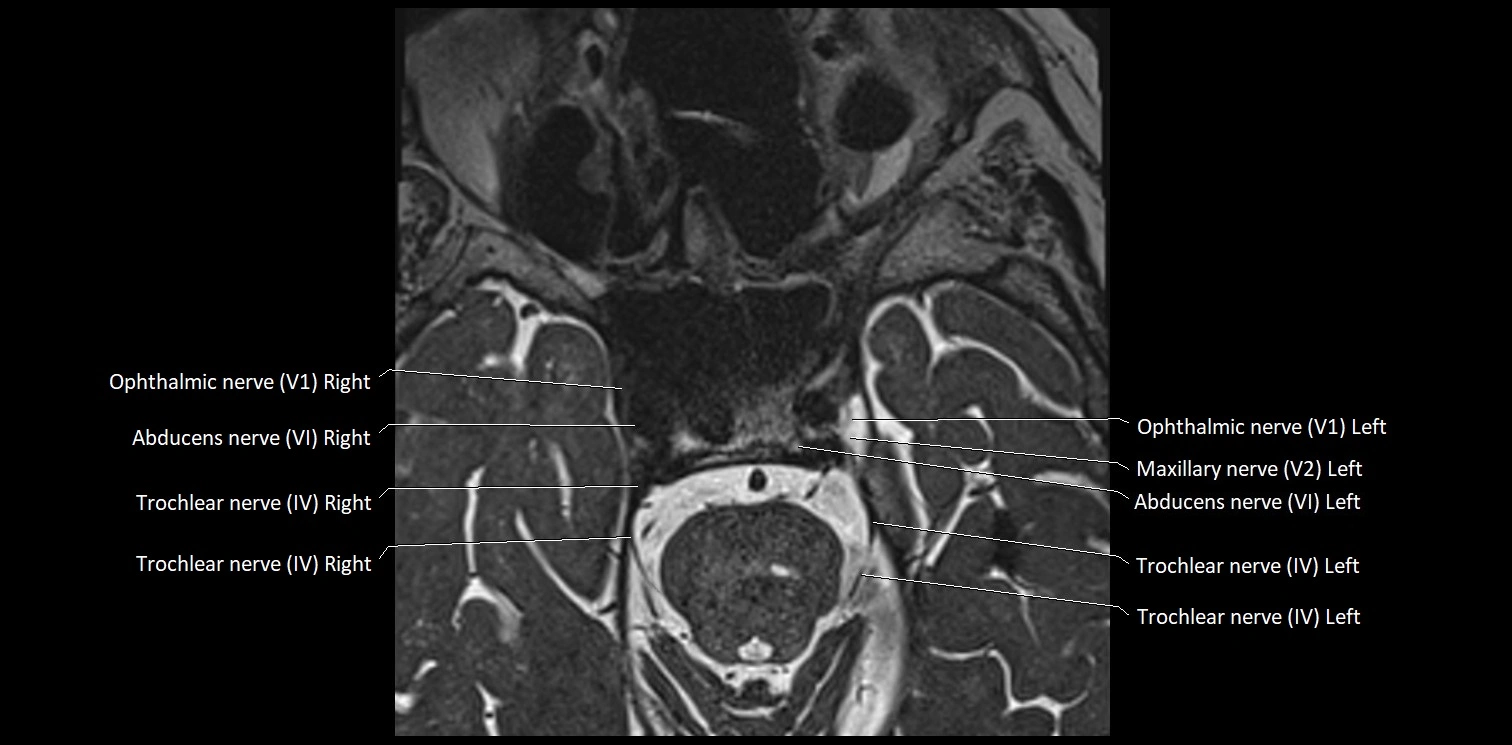

• The abducens nerve is a small, thin, linear structure

• Best visualized on high-resolution T2-weighted 3D MRI sequences (e.g., FIESTA or CISS)

• Seen as a hypointense (dark) line running from the brainstem at the pontomedullary junction, traversing the prepontine cistern, and entering Dorello’s canal under the petrosphenoidal ligament, then into the cavernous sinus, and finally the orbit

• May be challenging to visualize in standard MRI due to its small size

• Pathology may be inferred by absence, displacement, or enhancement of the nerve